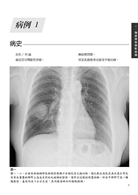

病例1 轉移性肉瘤(Metastatic sarcoma) 3